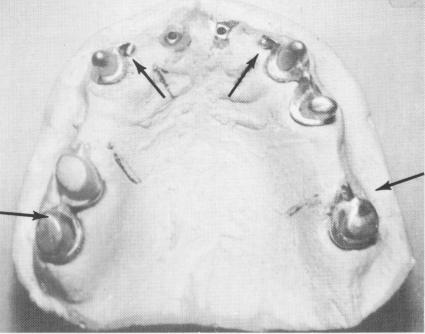

The master stone model was then made. Duplicate internally threaded implant posts were used as part of the mesostructure framework for the completion of the superstructure (Fig. 10-197). Obliquely-set channels were made in various strategically located portions of the mesostructure and superstructure wax-ups, and female internally threaded inserts were placed into the wax patterns before the wax frameworks were cast.

Fig. 10-196. A plaster index picks up the superstructure and mesostructure. Also seen are two duplicate implant shafts.

Fig. 10-197. The master stone model. Oblique channels were made at strategic areas in the mesostructure (arrows). (From Linkow, L. I.: Maxillary endosseous implants, Dent. Concepts 10[1 1:14-24, 1966.)